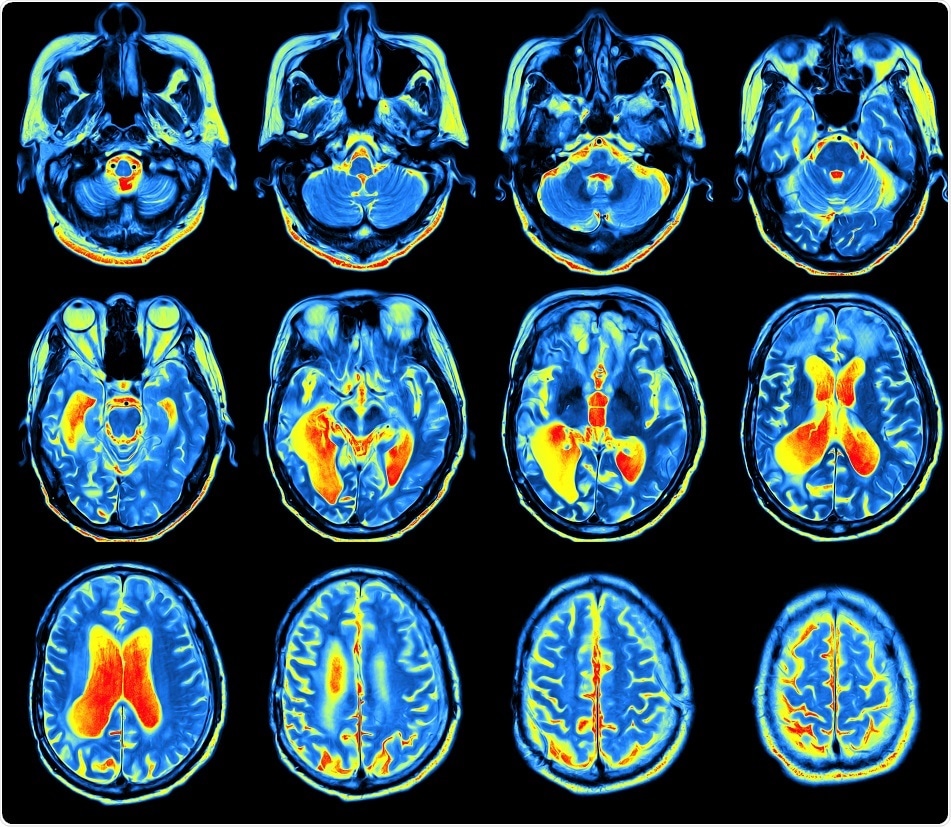

Credit: MriMan/ Shutterstock.com

The study, which was published in the journal Neuron, suggests that it is possible to build up a map of the connectome---the connections in the brain---by examining conventional brain scans obtained using a magnetic resonance imaging (MRI) scanner.

A conventional MRI scan provides a single image of the brain that enables the calculation of multiple structural features of the brain; i. e., each region of the brain can be described using nearly ten distinct characteristics.

The team built up a map indicating how well connected the major connection points, called “hubs,” between different regions of the brain network were, by utilizing the morphometric similarity networks (MSNs).